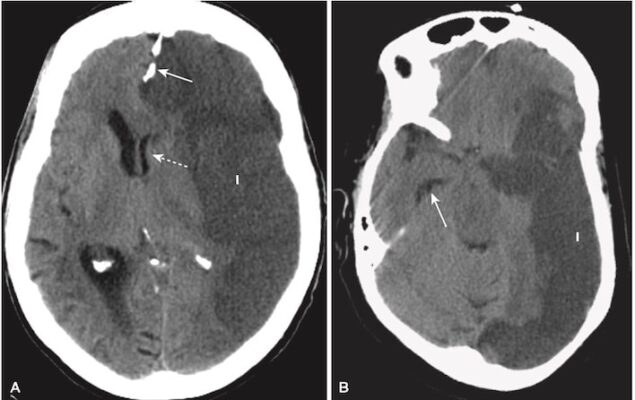

- Nhận biết máu tụ dưới màng cứng cấp tính (Hình 9)

- Trên CT, máu tụ dưới màng cứng cấp tính có hình lưỡi liềm, các dải ngoài não có đậm độ cao có thể băng ngang các đường khớp sọ và vào khe liên bán cầu. Máu tụ không vượt qua đường giữa.

- Điển hình, máu tụ dưới màng cứng lõm vào trong về phía não (máu tụ ngoài màng cứng lồi vào trong) (xem Hình 9, A).

- Sau một thời gian và khi máu tụ chuyển sang bán cấp, hoặc nếu máu dưới màng cứng được trộn với dịch não tủy có độ đậm đặc thấp hơn, chúng có thể biểu hiện đồng tín hiệu/cùng đậm độ (isodense) so với phần còn lại của não, trong trường hợp đó cần tìm các rãnh não bị ép hoặc biến mất hoặc bị đẩy lệch khỏi mặt trong xương sọ như các dấu hiệu của SDH (xem Hình 9, B).

- Các máu tụ dưới màng cứng có thể biểu hiện một mức dịch- dịch sau 1 tuần, khi các tế bào lắng xuống dưới huyết thanh.

- Tụ máu dưới màng cứng mạn tính

- Tụ máu dưới màng cứng mạn tính là những tụ máu xuất hiện hơn 3 tuần sau khi bị chấn thương.

- Máu tụ dưới màng cứng mạn tính thường có đậm độ thấp so với phần còn lại của não (xem Hình 9, C).